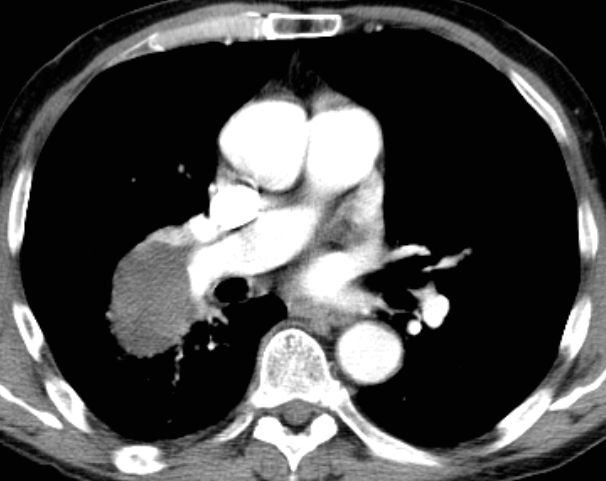

65-jähriger Mann mit einem SCLC rechts zentral, G3,Ki67 90%, chromogranin – negativ, CD56 negativ, CD45 negativ, Pankeratin z.T. positiv.![]() |

![]() |